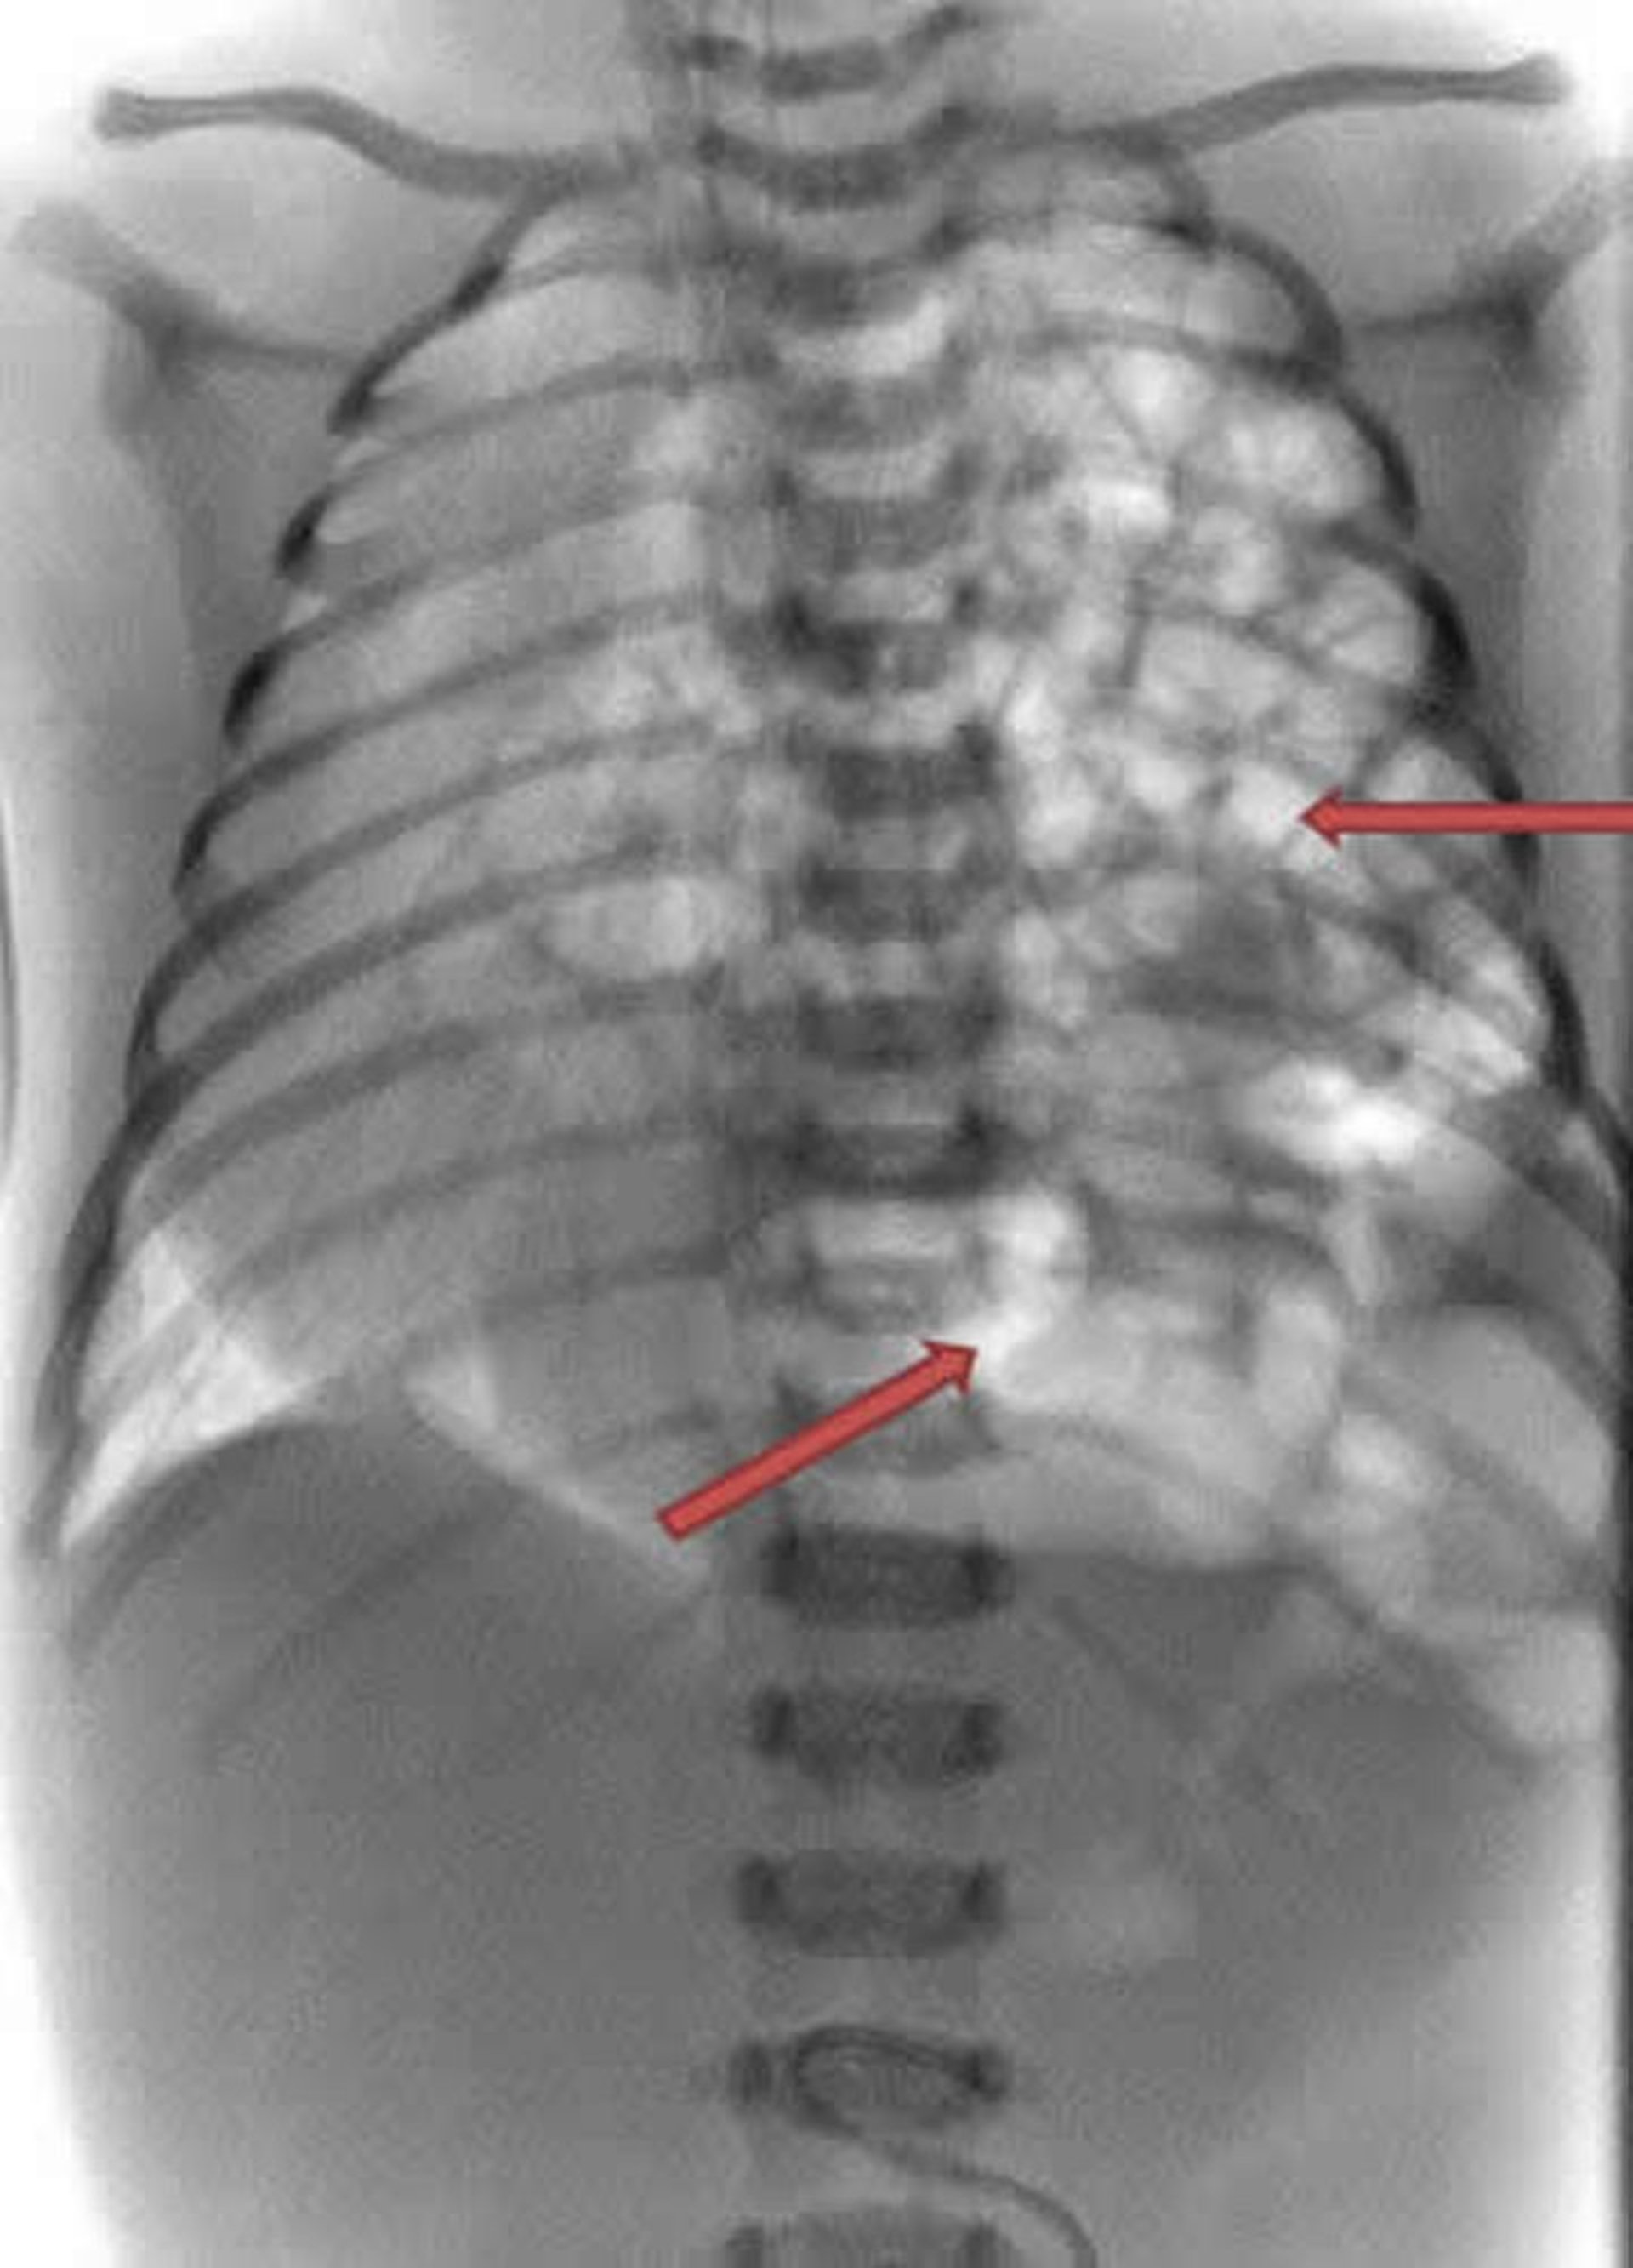

Hérnia diafragmática

Esta radiografia de um recém-nascido mostra que os intestinos (curvaturas brancas) estão saindo pelo lado esquerdo do tórax (setas).